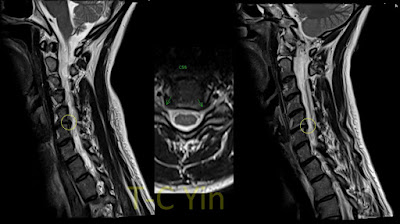

| 第三腰椎到第一薦椎在外院施行了鋼釘植入椎體融合手術 |

我幫她照了X光,病患從第三腰椎至第一薦椎被植入鋼釘做了椎體融合固定手術

術後的脊椎X光,顯示脊椎型態仍處於嚴重不平衡的狀態,第十二胸椎還有進一步的壓迫性骨折

| 手術後,身體仍嚴重前傾,駝背,且背痛持續 |